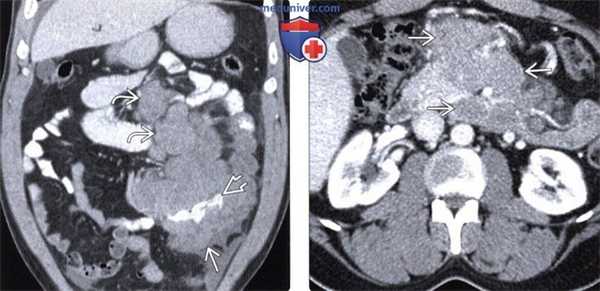

(Слева) При КТ с контрастным усилением на реформатированном изображении в корональной плоскости у пациента со СПИДом с низким уровнем CD4 выявлено диффузное утолщение стенки тонкой кишки, а также сопутствующий асцит. Изменений со стороны кишечника при последующих исследованиях не выявлено, была заподозрена авиум-микобак-териальная инфекция.

(Справа) На аксиальном срезе у ВИЧ-положительного пациента с лихорадкой, диареей в течение трех недель и потерей веса выявлены множественные увеличенные лимфатические узлы с измененной структурой, в том числе забрюшинные и брыжеечные. Биопсия подтвердила авиум-микобактериальную инфекцию. (Слева) На аксиальном КТ срезе (с контрастом) видны множественные очаги в селезенке и, менее выраженные, в печени. И печень, и селезенка увеличены.

(Справа) У этого же пациента выявлены множественные гиподенсные увеличенные лимфатические узлы. Эти находки позволили сделать вывод о распространенной микобактериальной инфекции.